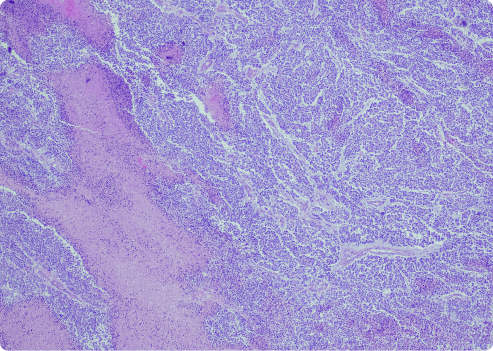

This variant has dense fibrous tissue and fewer cells. Desmoplastic cells are hard to identify. They lack clear patterns. These types of mesothelioma cells form dense nodules of connective tissue in tumors. This can make diagnosis more difficult.

- At least 50% of the tumor consists of nodules with dense fibrous tissue.

- Areas with increased cell activity show sarcomatoid features.

- Neoplastic spindle cells have spread to the lungs or chest wall.

- There is evidence of metastasis to nearby fat tissue, skeletal muscle or the lungs.

- The p53 tumor suppressor gene protein is present.